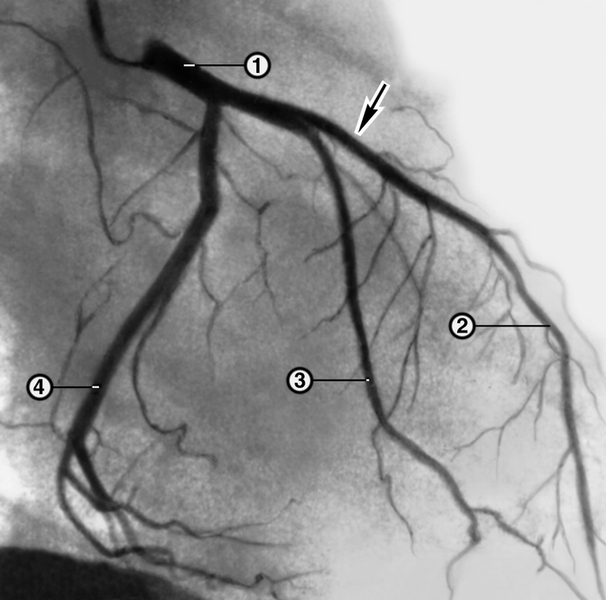

Особенности и диагностика левостороннего кровотока